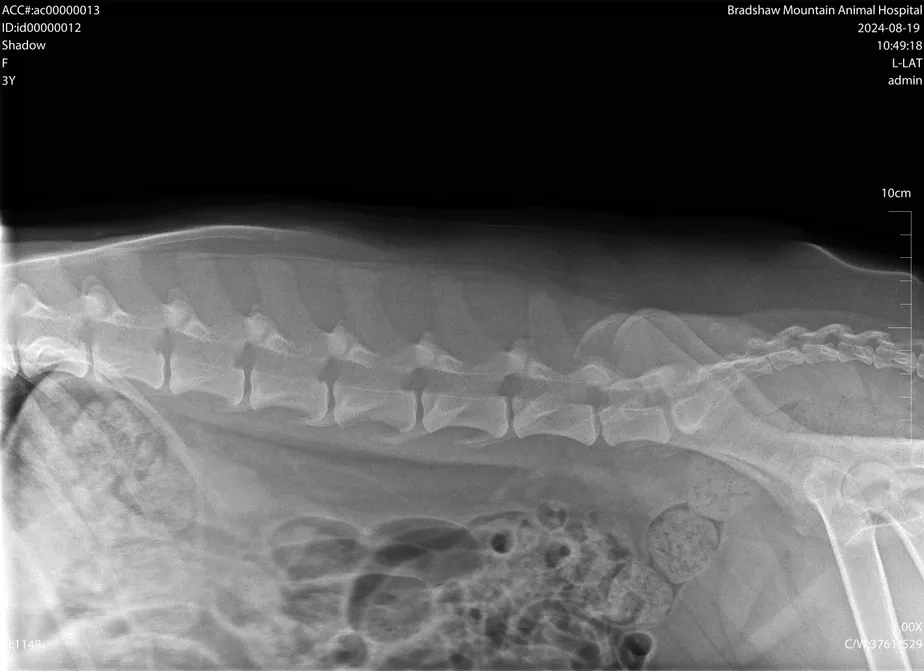

Veterinarians use radiology to take images of the chest, abdomen, and musculoskeletal system to diagnosis certain diseases. Here at Bradshaw Mountain Animal Hospital we have a fully equipped digital radiology system.